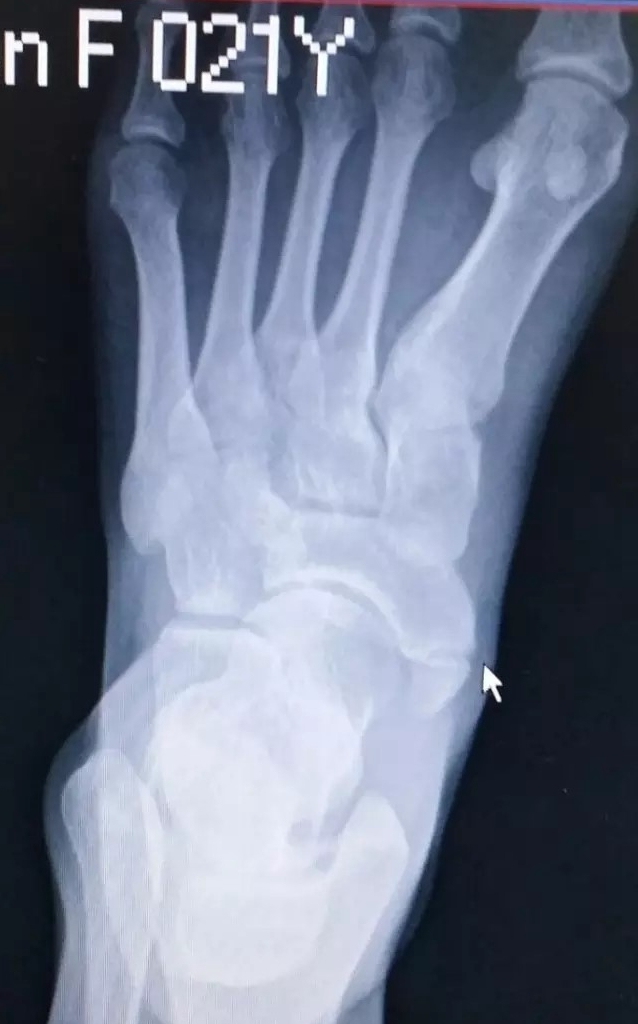

当发生足副舟骨疼痛时,首先要拍X光确诊,并确定分型。

副舟骨损伤多见于青壮年男性,常见发生在足内翻崴脚扭伤后。此时胫骨后肌突然收缩或将在副舟骨上的附着点撕脱。